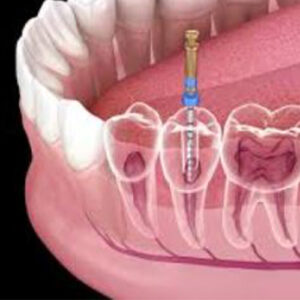

درمان ریشه فرآیندی است که طی آن پالپ یا عصب آسیبدیده دندان برداشته شده، کانالهای ریشه تمیز، ضدعفونی و سپس پر میشوند. پالپ دندان شامل عصبها، رگهای خونی و بافت همبند است و زمانی که به دلیل پوسیدگی عمیق، ضربه یا ترک دندان دچار عفونت شود، نیاز به درمان ریشه خواهد داشت.

معاینه و عکسبرداری

دندانپزشک با معاینه بالینی و گرفتن عکس رادیولوژی، میزان آسیب و تعداد کانالهای ریشه را بررسی میکند.

برداشتن پالپ عفونی

دندانپزشک با ایجاد سوراخی کوچک در تاج دندان، پالپ عفونی را خارج میکند.